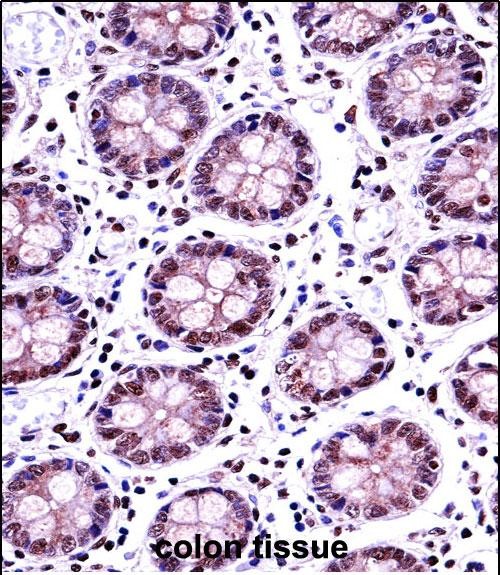

| IHC | 1/100-1/500 | Human,Mouse,Rat |

| Immunogen | This TERF2 antibody is generated from rabbits immunized with a KLH conjugated synthetic peptide between 308-337 amino acids from the Central region of human TERF2. |